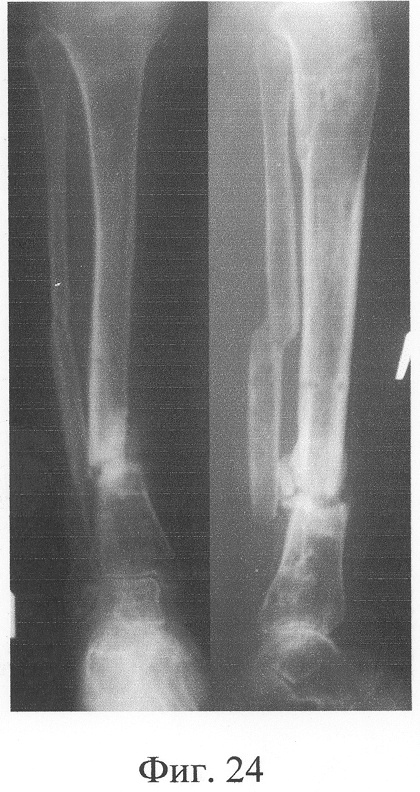

Одномоментно выполнены операции: резекция ложных суставов обеих большеберцовых костей, резекция левой малоберцовой кости, комбинированный чрескостный остеосинтез костей обеих голеней, костная пластика ложных суставов деминерализованным костным аллотрансплантатом из трубчатой кости, предварительно в лабораторных условиях заселенным аутологичными мезенхимными стволовыми клетками, выделенными из костного мозга пациентки, с плотностью заселения 7-10 млн на 1 см3 трансплантата. В послеоперационном периоде потребовалась дополнительная коррекция положения фрагментов на правой голени, что привело к смещению трансплантата из костного паза. Дренажи удалены на 3-е сутки, швы сняты на 15 сутки, антибактериальная терапия под контролем клинического фармаколога с учетом анамнеза. Ходьба с дополнительными средствами опоры с 7 суток послеоперационного периода. Компенсация укорочения бедра обувью (фиг.16-17 – клинические и фиг.18-19 – рентгенологические данные в процессе лечения, трансплантаты отчетливо видны на рентгенограммах, отмечается нарастание плотности костной ткани в области трансплантатов).

Аппарат внешней фиксации с левой голени демонтирован через 3 месяца после операции при клинико-рентгенологической картине сращения перелома. Аппарат внешней фиксации с правой голени демонтирован через 7 месяцев после операции при клинико-рентгенологической картине сращения перелома (фиг.20-25 – результат лечения). При рентгенологическом и томографическом контроле в трансплантатах отмечалось постепенное нарастание плотности костной ткани с формированием костной мозоли на всем протяжении между трансплантатом и костными фрагментами (фиг.26-29 – динамика данных компьютерной томографии правой голени: отмечается нарастание плотности костной ткани в области трансплантатов и формирование регенерата между смещенным трансплантатом и костными фрагментами; фиг.30-33 – динамика данных компьютерной томографии левой голени: отмечается нарастание плотности костной ткани в области трансплантатов и формирование регенерата между трансплантатом и костными фрагментами).